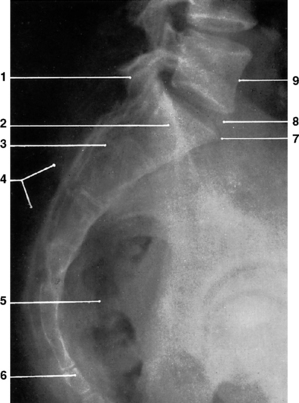

Fig. 9.5 Cervical vertebrae: oblique anteroposterior projection.

C – Right intervertebral foramina

(From Bryan 1996.)